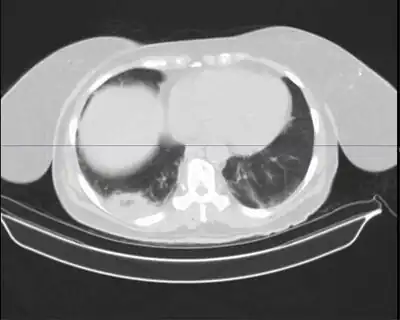

Mycobacterium nebraskense presenting as cavitary lung lesion